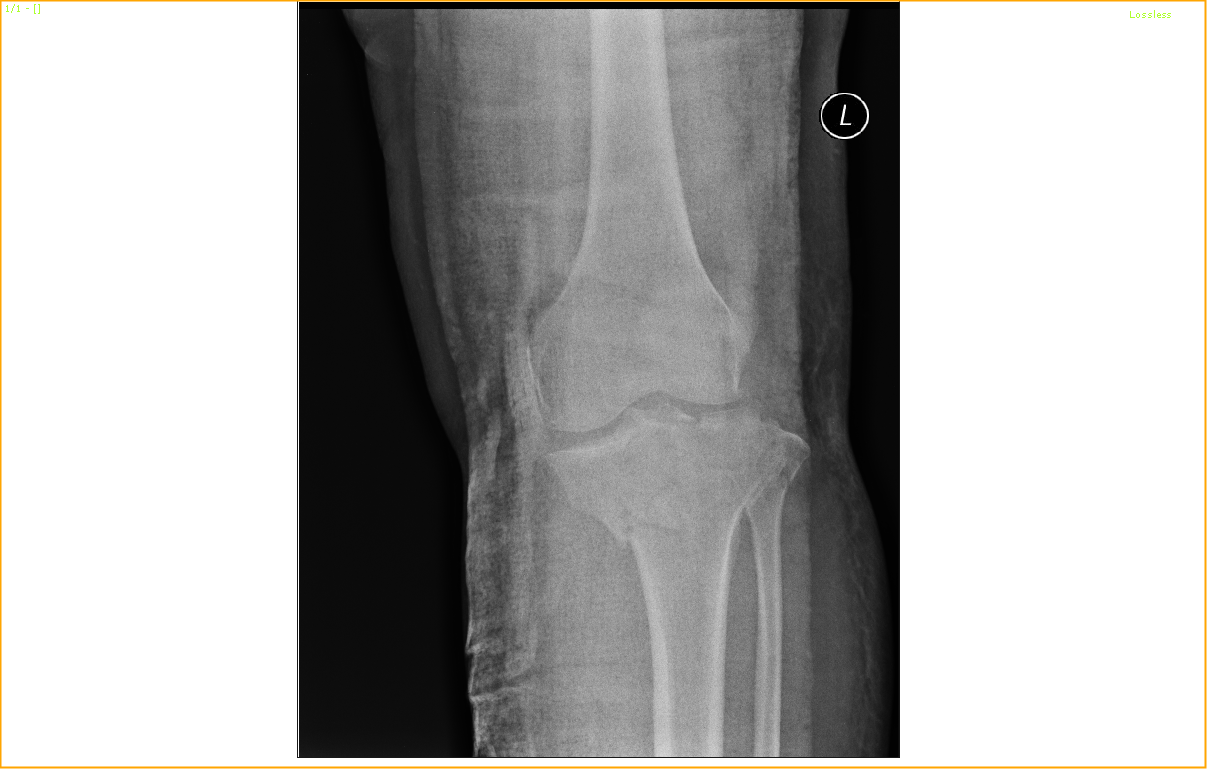

A Tibial plateau fracture with knee joint involvement in a 52-year-old lady!